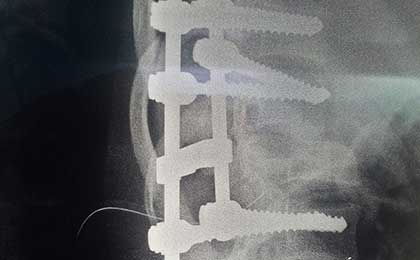

POST OP XRAY LAT

post op x ray lat 1

post op L5 S1 FIXATION

post op dorsolumbar fixation x ray